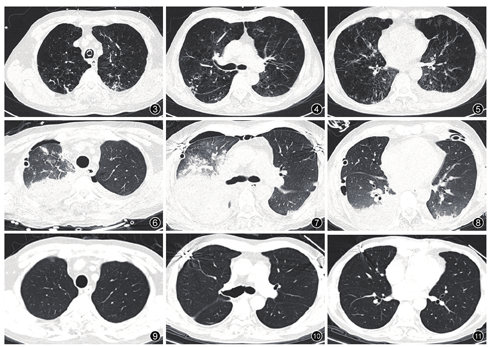

患者何某,男,68岁,因"反复咳嗽咳痰气促10年,加重1个月余",于2015年3月2日带经口气管插管接呼吸机辅助通气转入我科。转入诊断:(1)慢性阻塞性肺疾病(chronic obstructive pulmonary disease,COPD)急性加重期;(2)Ⅱ型呼吸衰竭 ;(3)双侧肺炎。入科后根据痰细菌培养(铜绿假单胞菌),予头胞哌酮钠舒巴坦钠治疗。5 d后患者病情改善,拔除气管插管后予无创通气辅助。无创通气5 d后因患者感染加重、呼吸衰竭,再次予插管行有创通气及继续抗感染等治疗。经多学科讨论,根据病史、临床表现,胸部CT等确定患者为终末期COPD,符合肺移植入选标准。肺功能(6个月前外院行肺功能检查,因患者气促明显无法完成肺功能检查)。于2015年3月24日行"蚌式切口双肺移植术"。术中见双肺呈灰黑色并过度膨胀,内部和表面充满散在肺大泡,全肺弹性和顺应性明显降低,局部有结节状表现,右中下胸膜粘连严重。受体切除肺组织病理:慢性支气管炎、肺大泡性肺气肿伴机化性肺炎。手术先左侧后右侧,供肺来源:公民逝世后器官捐献(donation after cardiac death,DCD)。术后体温38.2℃,右上肺纤支镜下可吸出大量脓血性分泌物,胸片示双肺渗出影,右上肺明显(图1),考虑与肺损伤及术后肺部感染进展有关。术后予美洛培南、万古霉素、卡泊芬净、更昔洛韦抗感染治疗,予甲泼尼龙、他克莫司、霉酚酸酯三联抗排斥治疗。术后第3天因病原学回报患者供体肺组织培养结果为耐甲氧西林金黄色葡萄球菌(meticillin-resistant Staphylococcus aureus,MRSA),表皮葡萄球菌、发酵乳杆菌,受体残肺组织培养为多耐药铜绿假单胞菌、粪肠球菌,予停万古霉素改用利奈唑胺抗球菌感染。术后第7天出现寒战发热,体温最高达40℃,血压100/50 mmHg[去甲肾上腺素0.6 μg/(kg•min),1 mmHg=0.133 kPa],诊断考虑:败血症、感染性休克,行血培养。血培养回报革兰阴性杆菌(鲍曼不动杆菌),使用美罗培南(6.0持续静脉输注)联合使用头胞哌酮钠舒巴坦钠(3.0静脉滴注q8 h)抗感染治疗,静脉免疫球蛋白治疗5d[剂量0.4 g/(kg•d)]及液体复苏、血管活性药物等抗休克治疗;同时,停用他克莫司、霉酚酸酯,予静脉甲基强的松龙(40 mg/d)抗排斥治疗。术后第17天患者体温逐渐下降至正常,循环稳定。根据病原学降级抗生素为头胞哌酮钠舒巴坦钠,加回他克莫司和霉酚酸酯抗排斥治疗(图2)。术后第22天拔出气管插管,予无创通气过度后转普通病房。术后3个月出院回家,胸部CT检查见肺部手术前后的影像学变化(图3,图4,图5,图6,图7,图8,图9,图10,图11),目前一般情况良好。